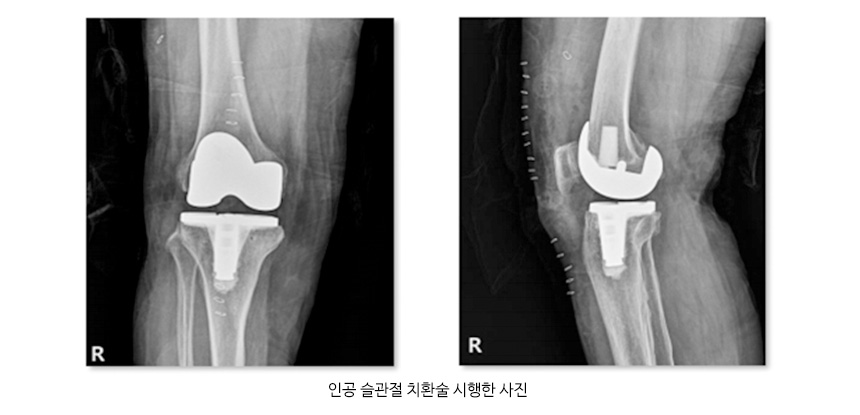

● 진단 퇴행성 관절염을 진단하기 위해서는 X-ray촬영을 통하여 관절염 여부를 판정하며, 동반된 연부조직의 이상이나 관절연골의 상태를 보기 위해 MRI 촬영을 하기도하며 혈액검사와 관절액을 검사하여 다른 원인에 의한 관절염의 여부를 확인하기도 합니다. ● 치료 퇴행성 관절염을 치료하기 위해서는 생활습관을 개선하고 약물요법으로 염증을 줄이고 재활치료를 시행하여 증상 완화와 근육위축 방지를 할 수 있으며, 비수술적 치료방법에도 불구하고 증상 호전이 없는 경우 관절경 및 인공관절 치환술을 시행하기도 합니다. 관절염 사진 및 인공슬관절 치환술 사진 ![]() ![]() |